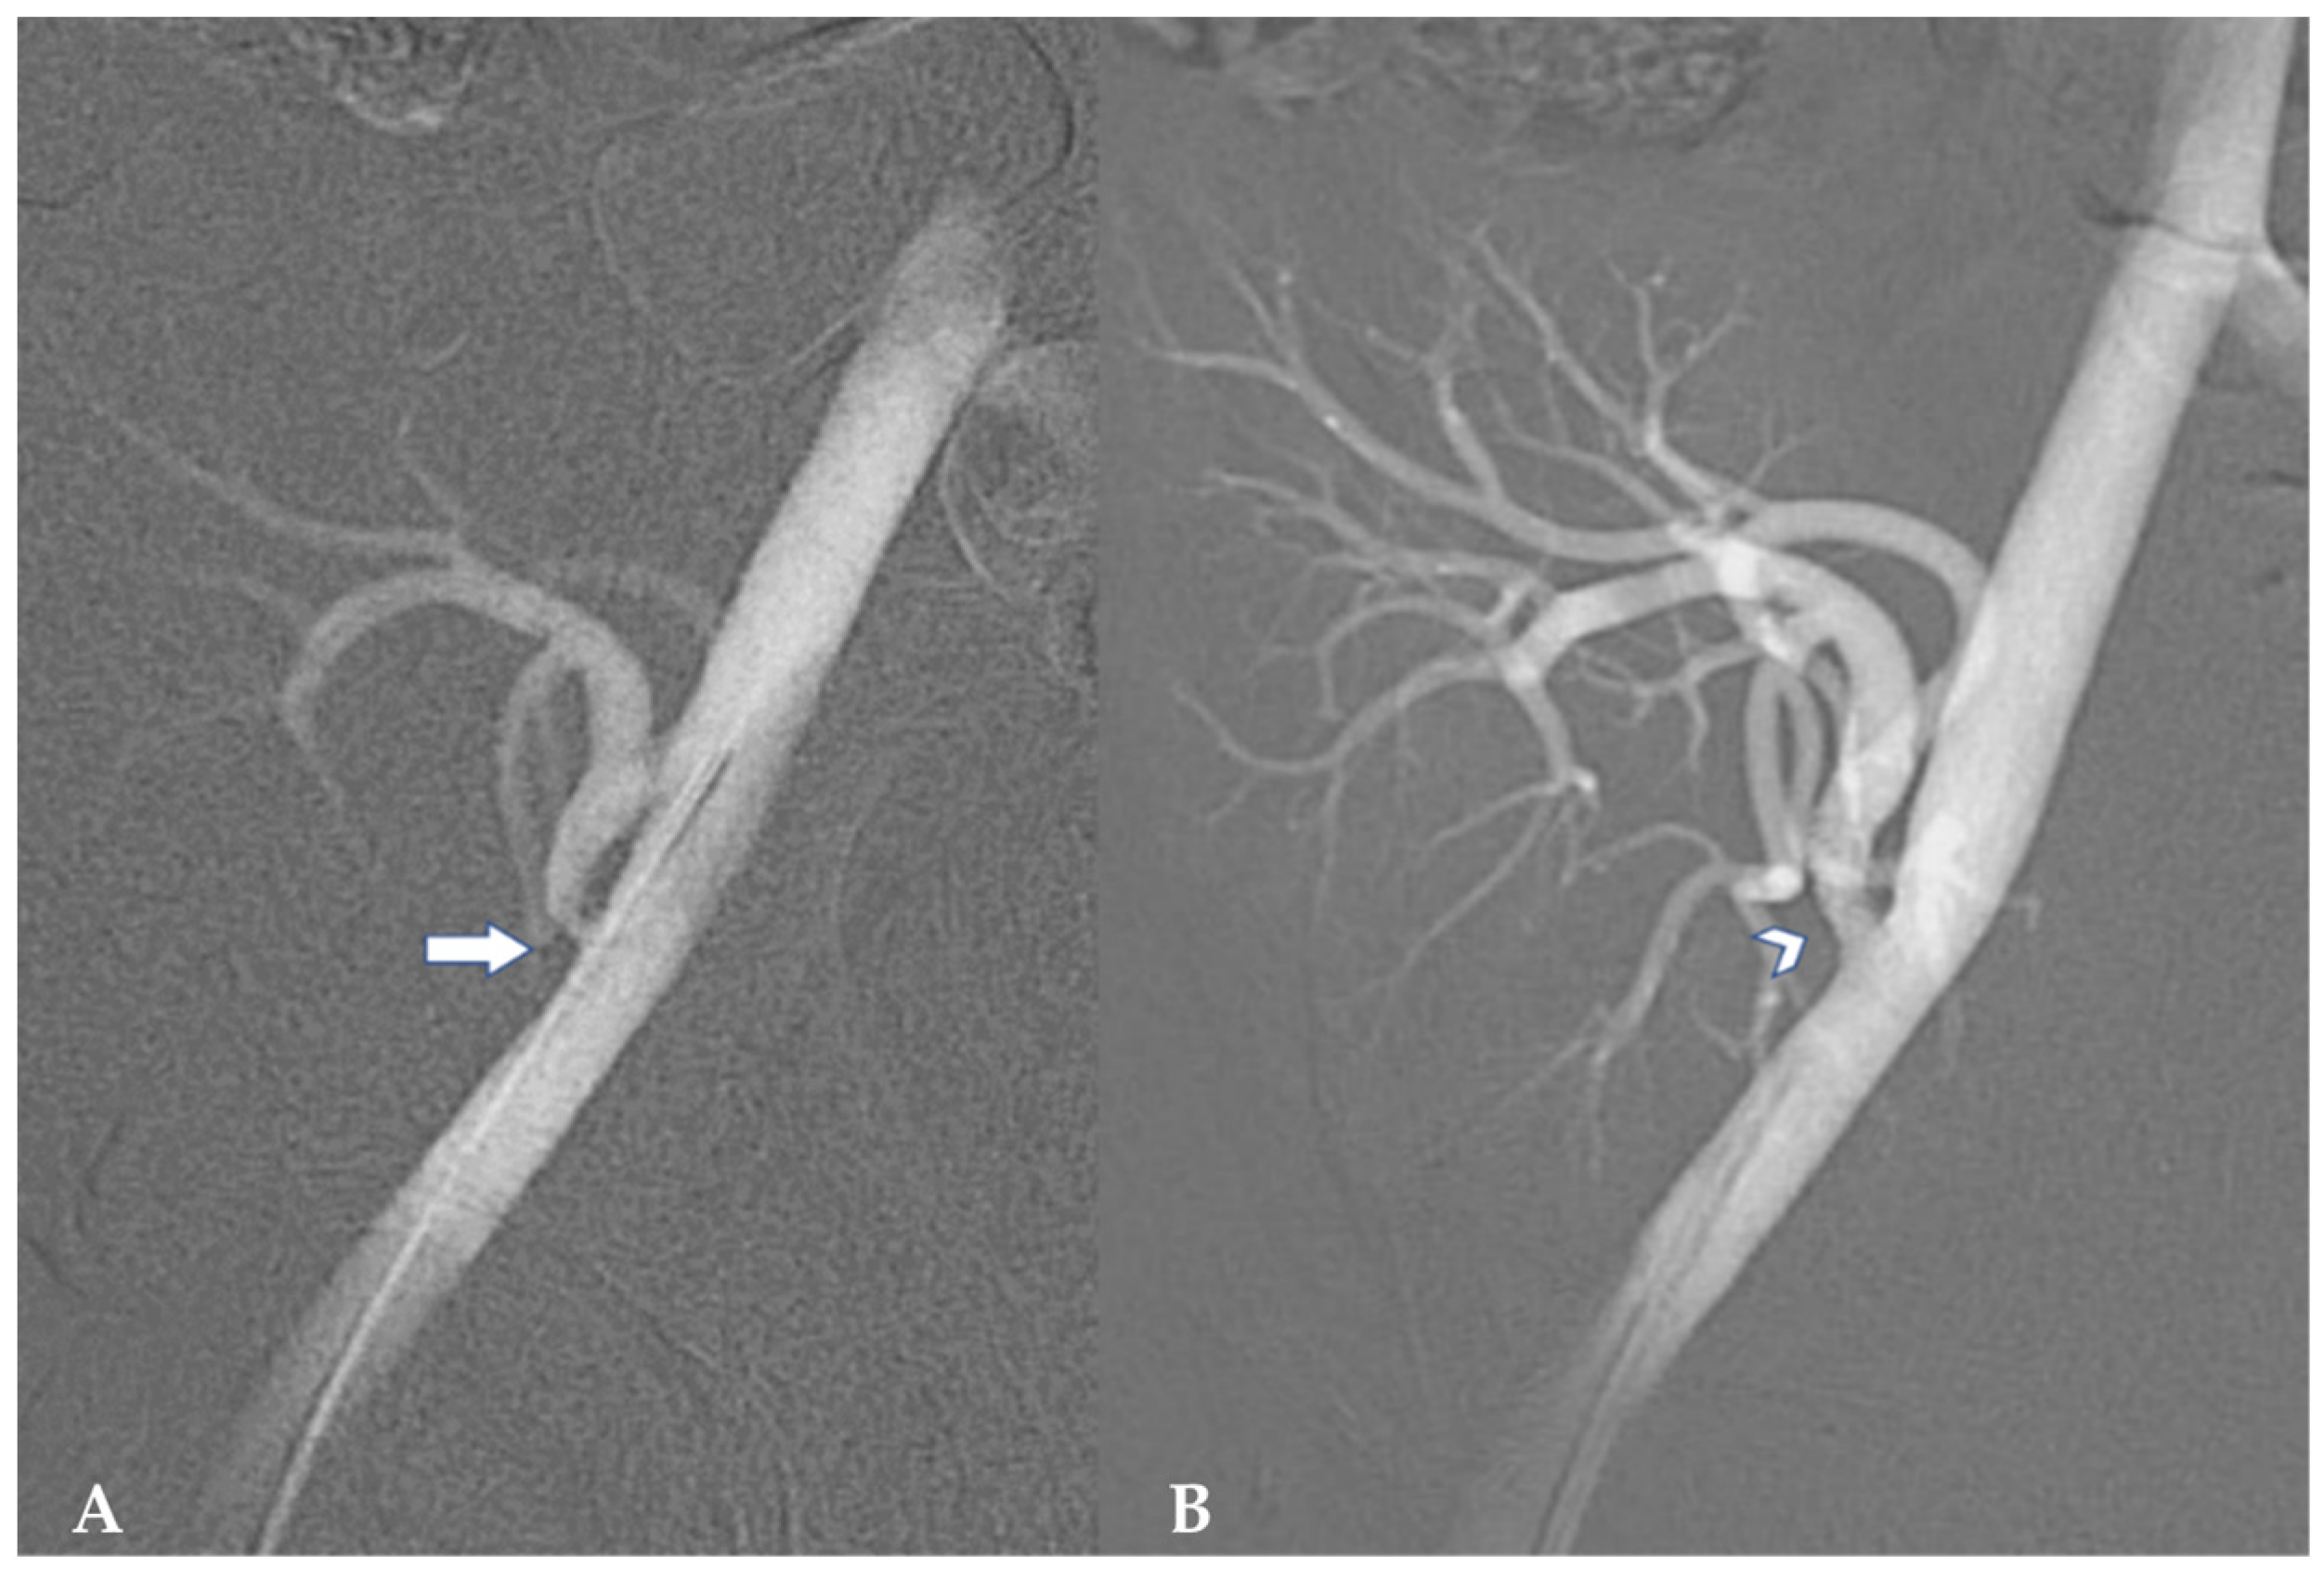

3.3. Arterial Aneurysm

- Ho, C.E.R.H.; So, W.Z.; Wong, J.; Tiong, H.Y. Successful repair of transplant renal artery aneurysm (TRAA). BMC Urol. 2023, 23, 129. [Google Scholar] [CrossRef]

- Maritati, F.; Pini, R.; Comai, G.; Bini, C.; Corradetti, V.; Mattiotti, M.; Ravaioli, M.; Pini, A.; La Manna, G.; Gargiulo, M. Anastomotic Pseudoaneurysm in Kidney Transplant: A Challenging Management for a Rare Entity. J. Endovasc. Ther. 2024, 31, 140–145. [Google Scholar] [CrossRef]